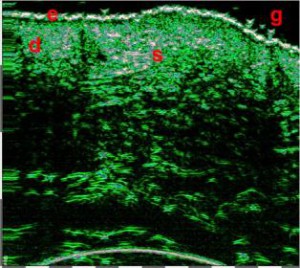

-Υπέρηχος Υψηλής Συχνότητας (HFUS) και Ιστολογία